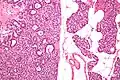

Micrographs